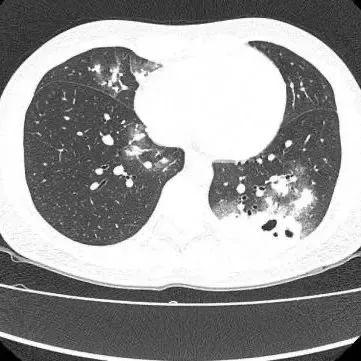

近日,30岁的夏女士(化名)因持续干咳一周到广医附属番禺中心医院呼吸科门诊就诊,胸部CT显示双肺多发感染伴多发空洞形成,收入呼吸与危重医学科一区住院治疗。

该科室刘知陶主任查房时,敏锐捕捉到CT上形似“鬼脸”的特殊影像(即“鬼脸征”),并伴有“晕伦征”,高度怀疑隐球菌肺炎。医生追问夏女士近期是否曾接触鸟类、禽类及饲养宠物,夏女士否认。

在影像学表现方面,典型CT表现是单发/多发结节伴“晕轮征”,结节液化坏死可形成空洞形似“鬼脸征”,空洞常为薄壁空洞、无液平。